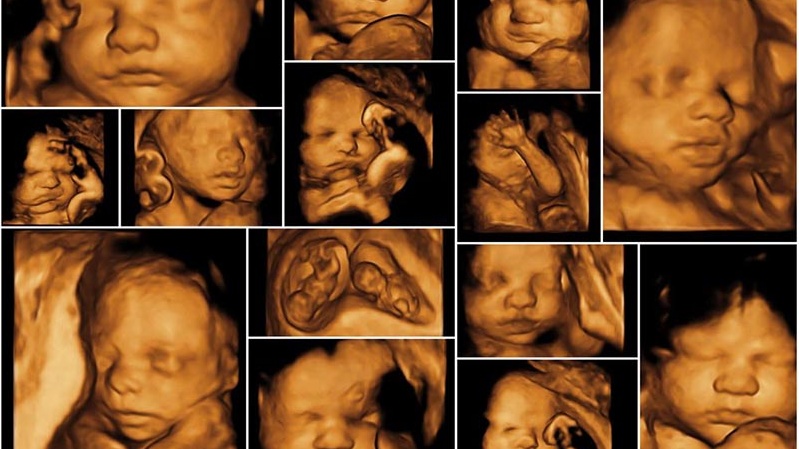

Nhờ siêu âm 4D, cha mẹ có thể thấy rõ các cử động và biểu cảm của thai nhi như cười, mếu, mút tay, nhăn mặt,... Ngoài ra, các chỉ số về sinh trắc và cấu trúc cơ thể thai nhi cũng được hiển thị, giúp bác sĩ phân biệt giữa hình ảnh bình thường và bất thường, từ đó đưa ra phương pháp xử trí phù hợp.

Thống kê cho thấy, siêu âm 4D có thể phát hiện dị tật với độ chính xác từ 80% đến 85%. Ngoài ra, kỹ thuật này cung cấp thông tin chi tiết về tình trạng bánh nhau, lượng nước ối, vị trí thai nhi và các chỉ số sinh trắc học. Mẹ bầu cũng có thể thấy rõ trạng thái của bé như mút tay, ngáp, ngủ và các đường nét cơ thể.

Khoảng thời gian siêu âm là dịp để mẹ tận hưởng niềm vui khi nhìn ngắm con từ trong bào thai.